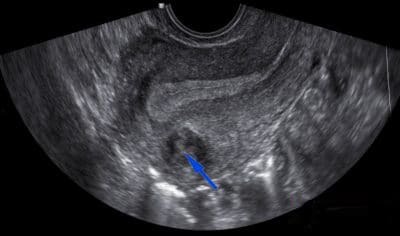

17

Q

Qual o diagnótico

A

Mioma